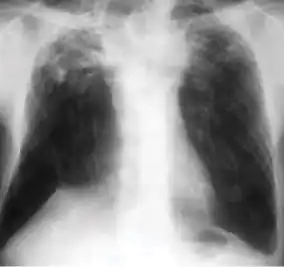

1. Infiltrate or consolidation - Opacification of airspaces within the lung parenchyma. Consolidation or infiltrate can be dense or patchy and might have irregular, ill-defined, or hazy borders.

-

Dense homogenous opacity in right, middle and lower lobe of primary pulmonary TB. -

Chest x-ray showing patchy opacification on the upper right and mid-zone lung with fibrotic shadows, as well as bilateral hilar lymphadenopathy. -